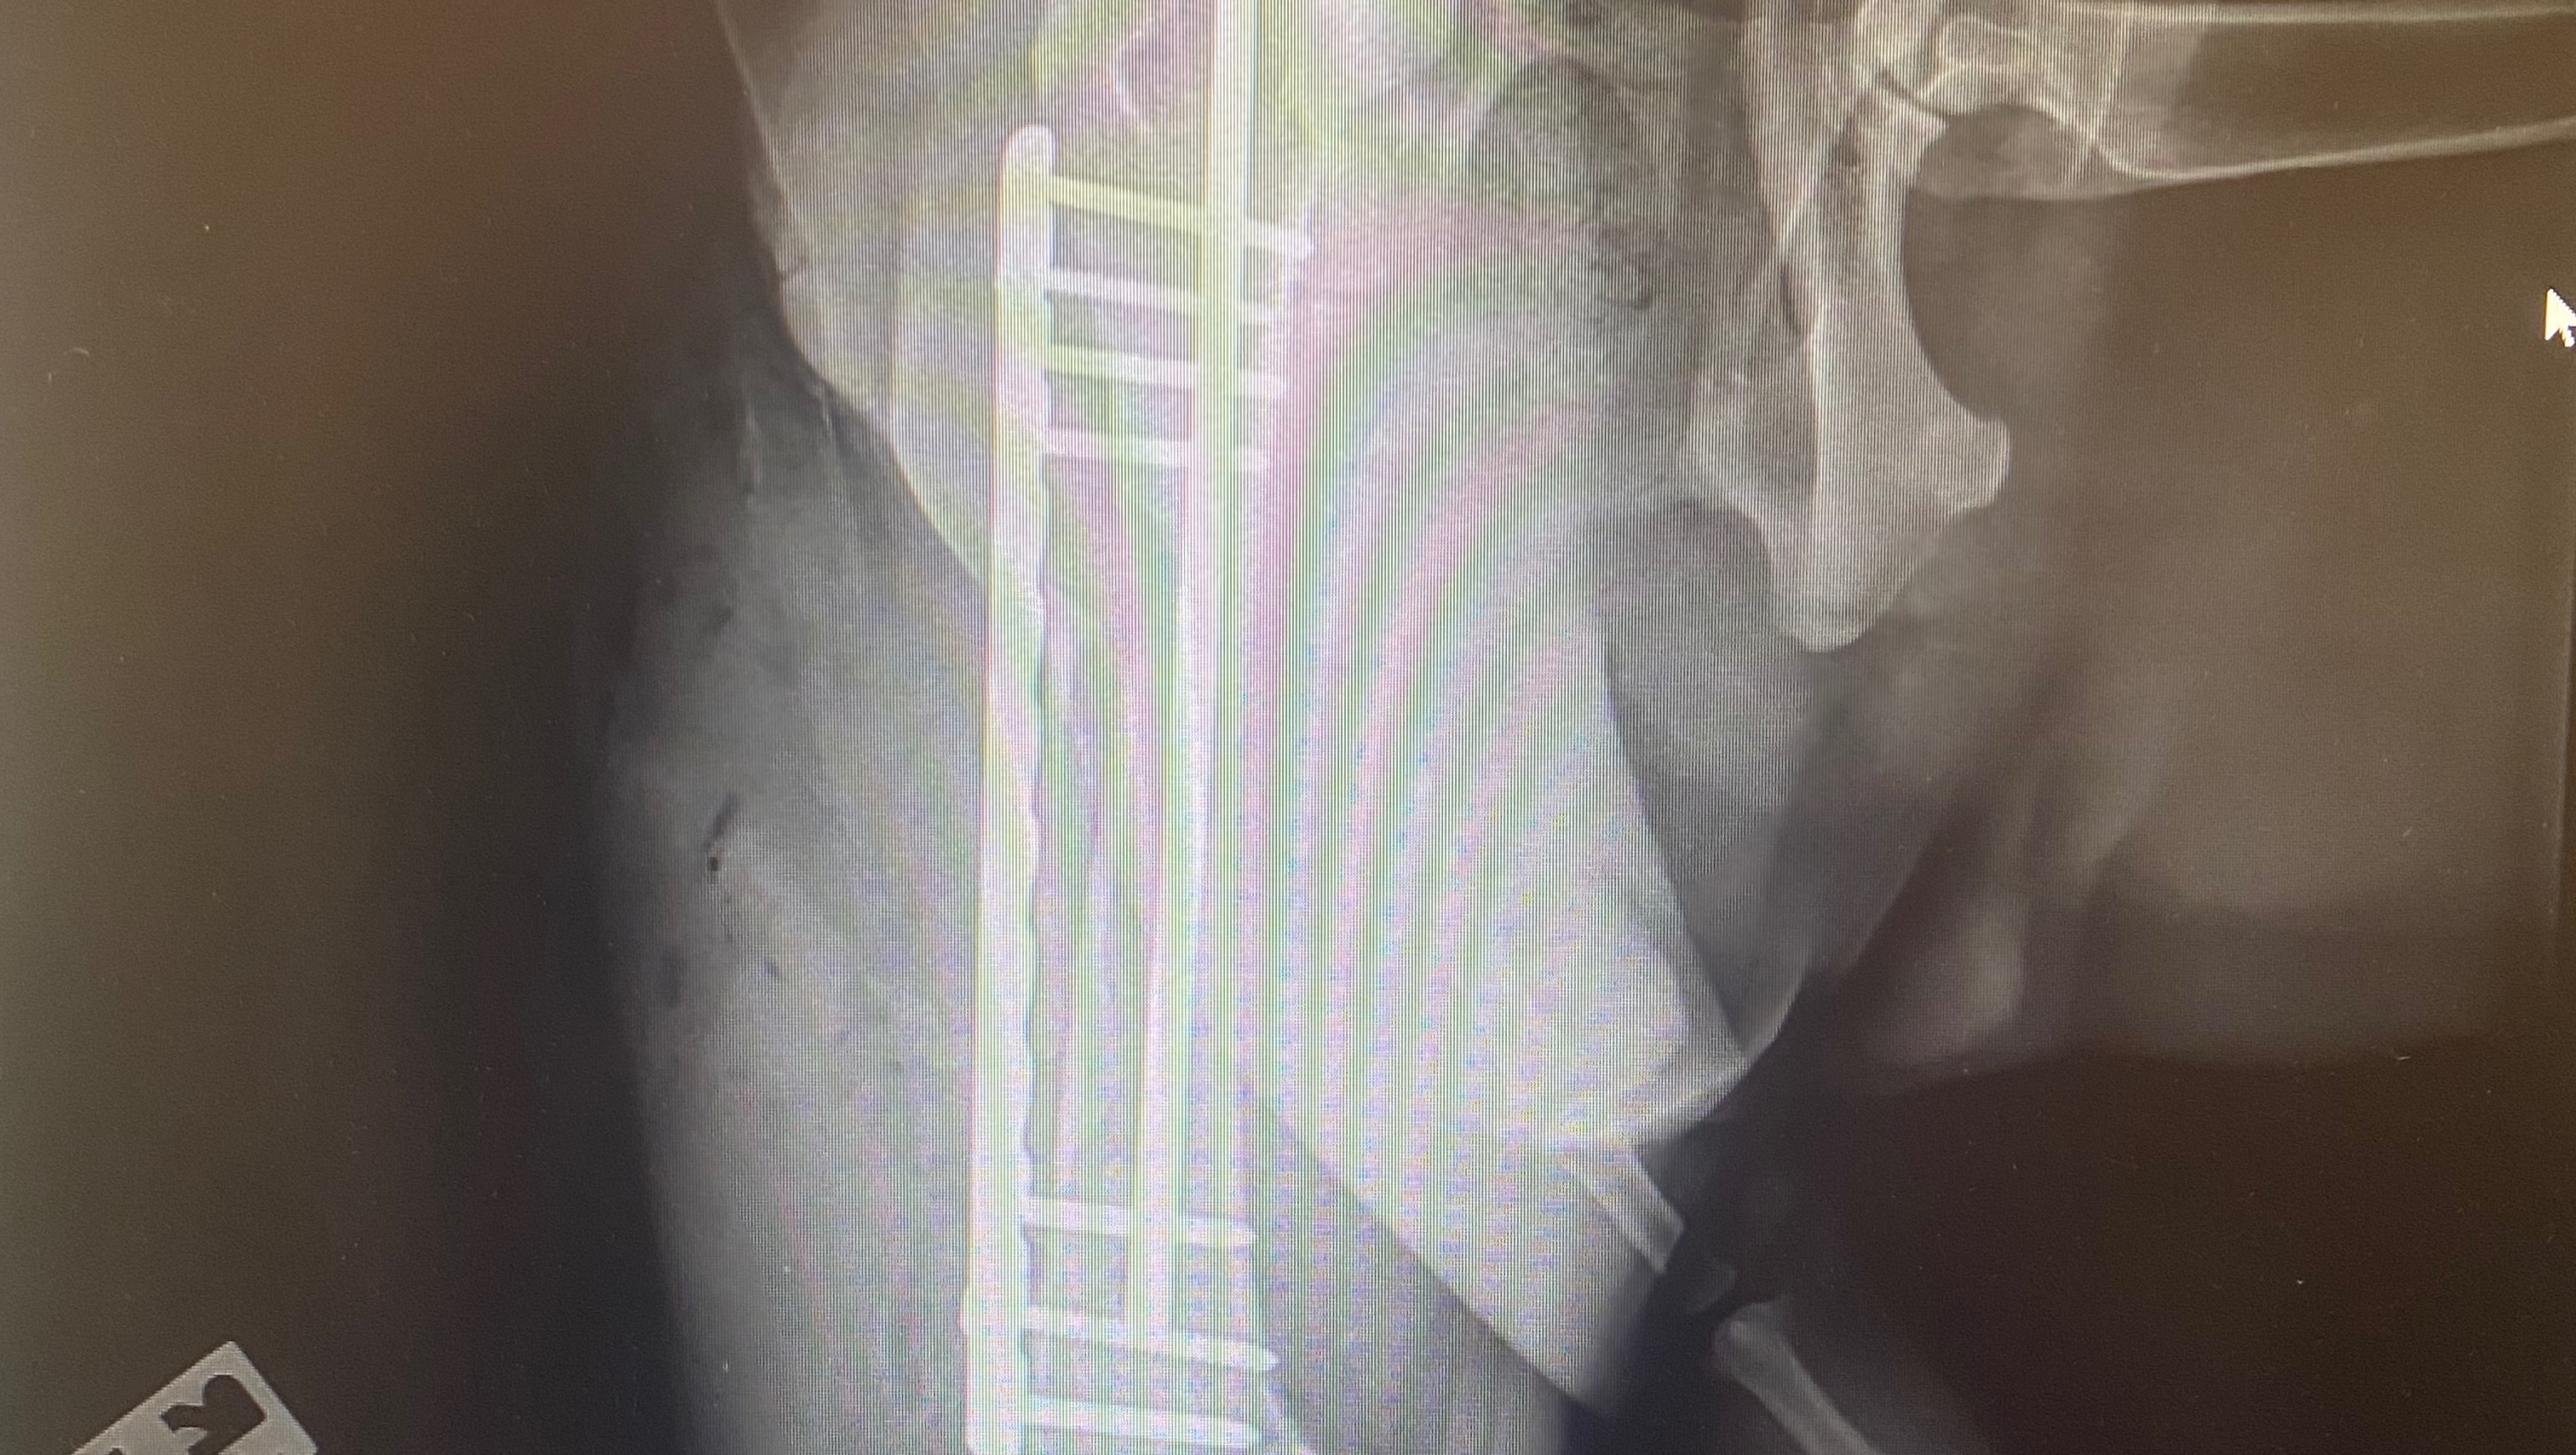

Titus suffered a comminuted Femur fracture and had to have emergency surgery and orthopedic implants to stabilize his leg. He also suffered a CCL tear as a result of the trauma.

Titus has had a very tough recovery since his injury and in ️October 2024, he suffered a major setback.

He began to be non-weight bearing on his leg. After several veterinary opinions, imaging, and medication trials, it was determined that the hardware that was placed in Titus leg, was now causing him an infection. So the orthopedic surgeon has said we need to remove the hardware.

Since long term antibiotic use isn’t something that is recommended, surgery is something that is needed, soon.